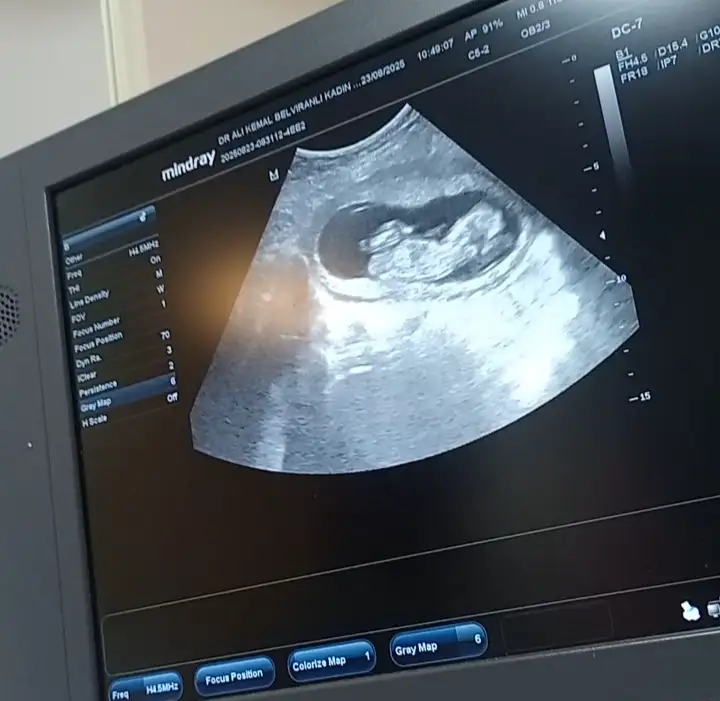

Merhaba yeni görüntüler var sizce ne olabilir doktorum bir tahminde bulundu ama sizin fikrinizi merak ediyorum

13+4 tahminde bulunabilir misiniz şimdiden teşekkür ederim.